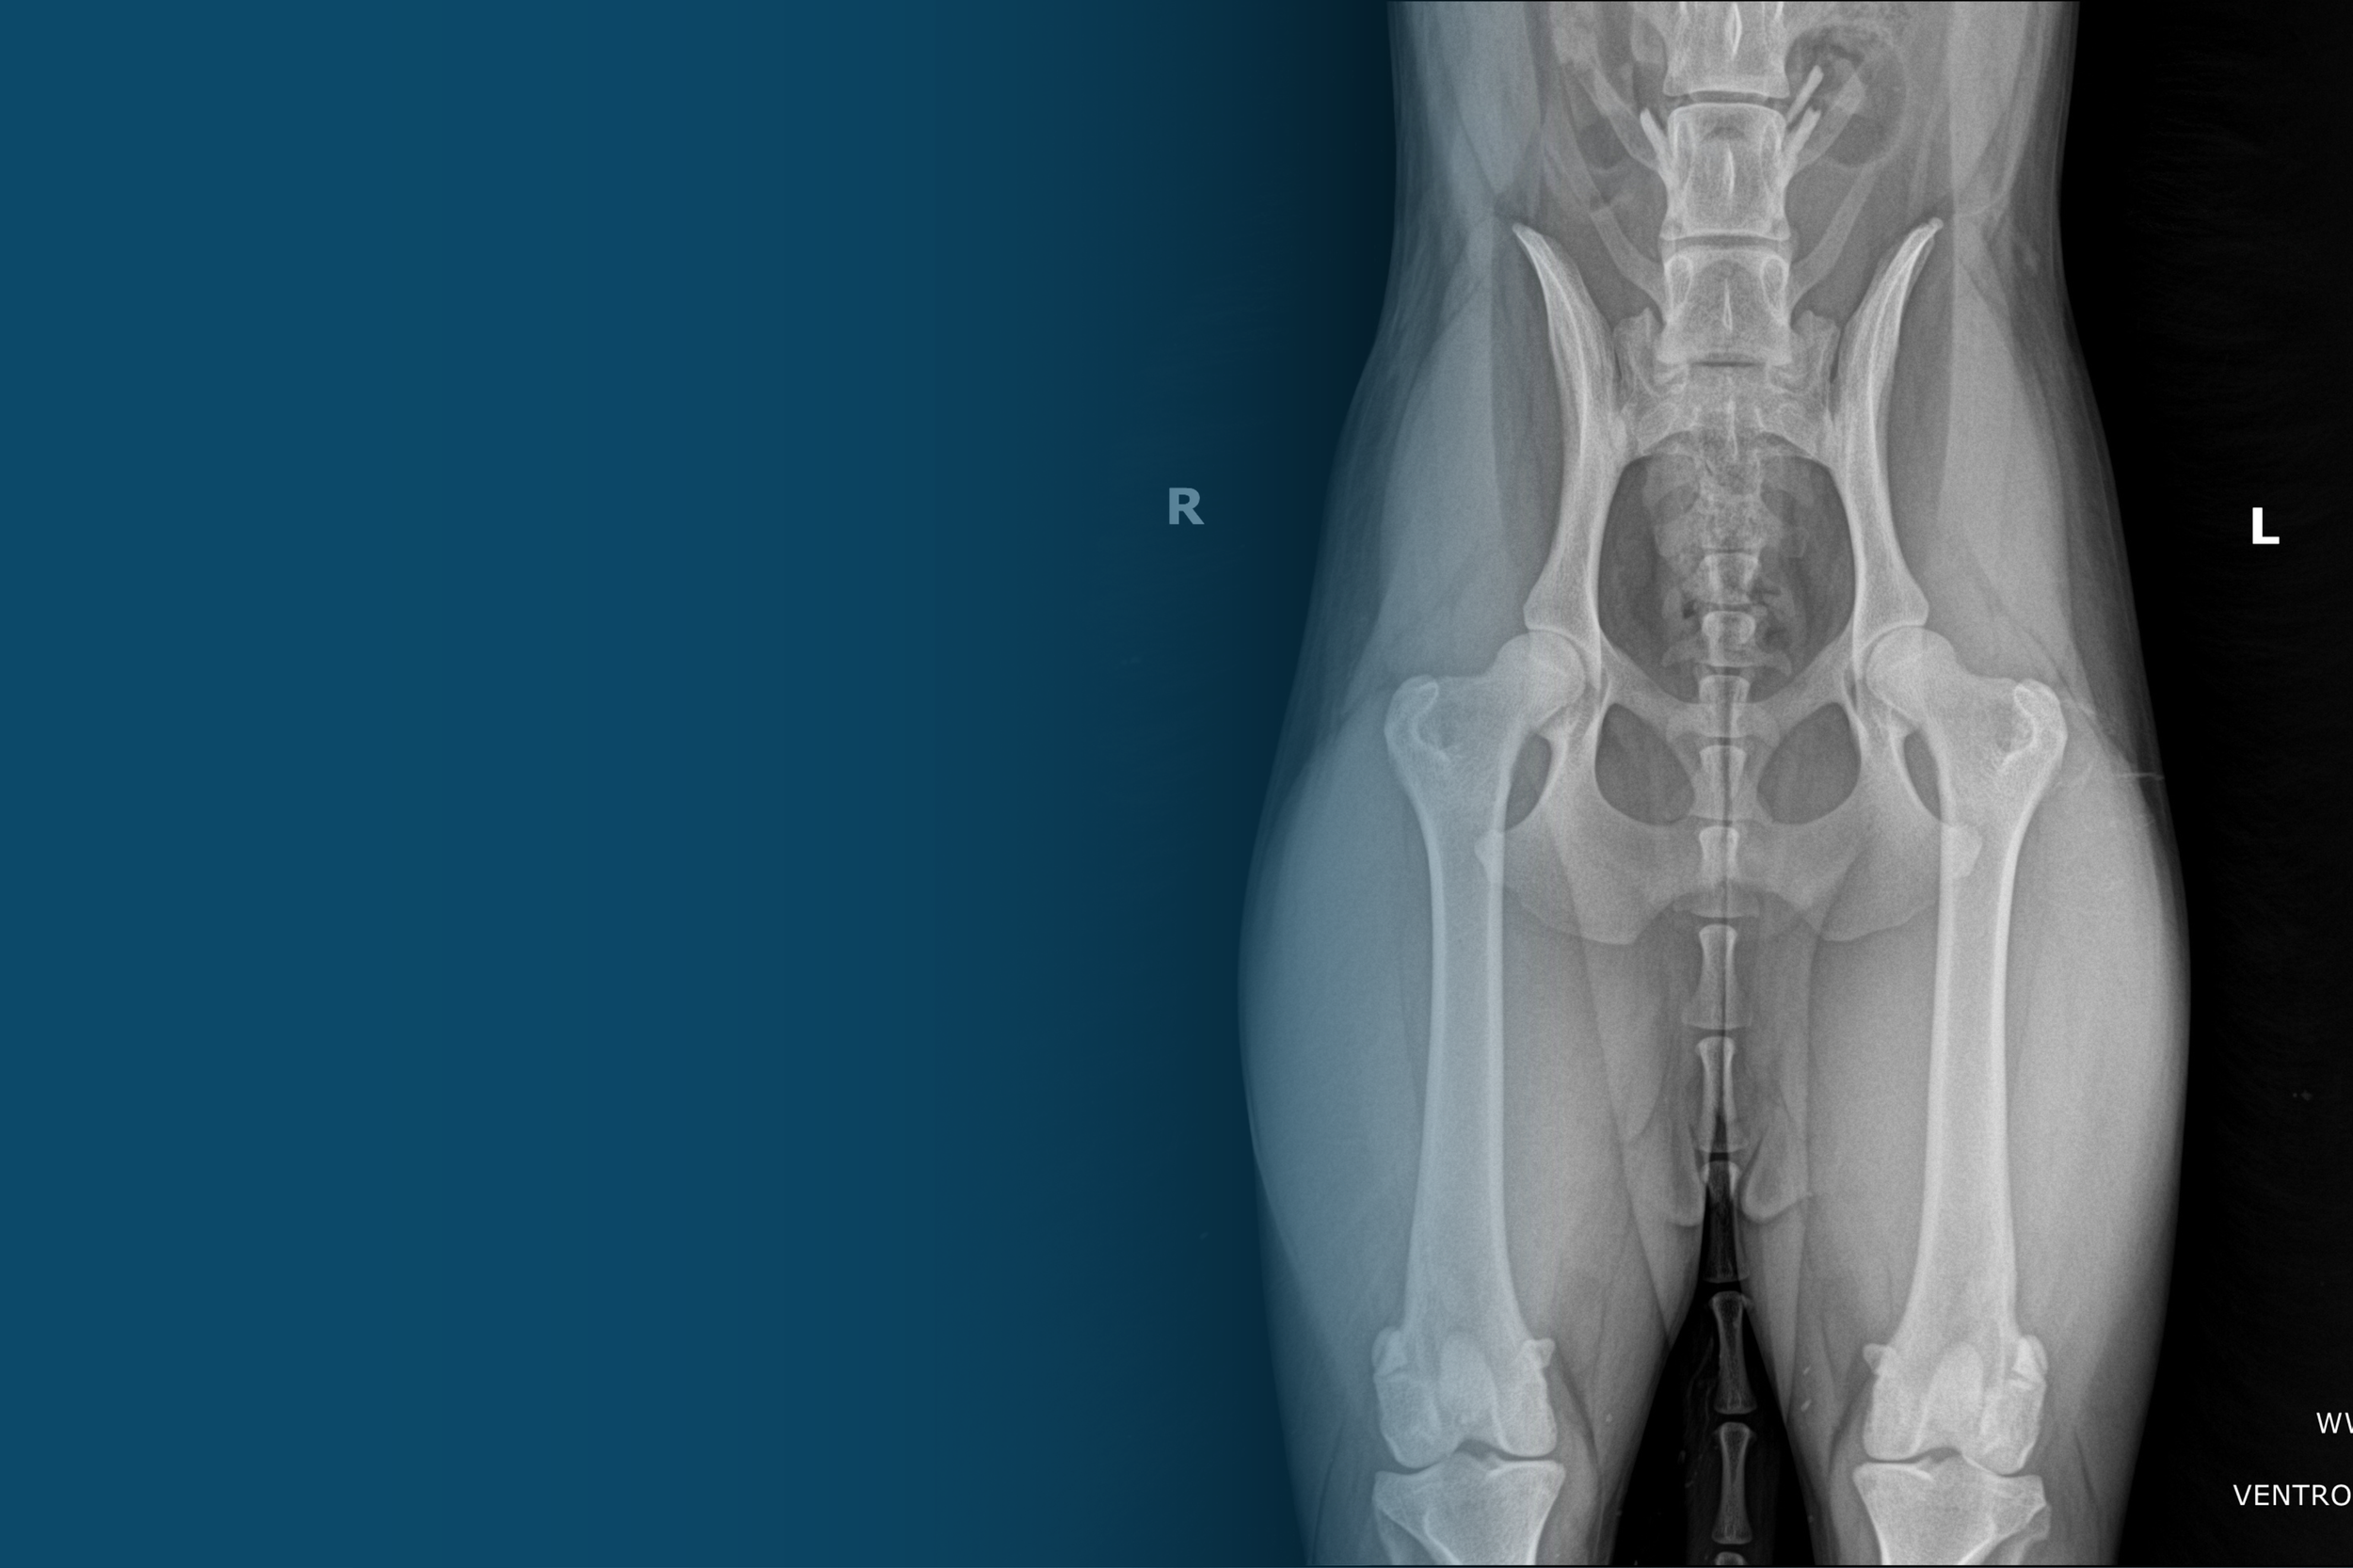

Orthopedic Health

• Hip Dysplasia Evaluation (OFA, PennHIP, or FCI)

Orthopedic Evaluations

• Elbow Dysplasia Evaluation

• Patellar Luxation Evaluation